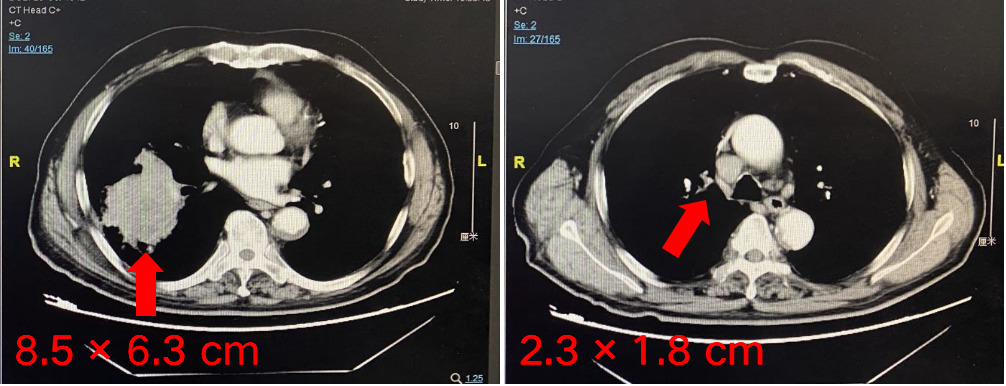

在2020年,替雷利珠单抗先后公布了一线鳞状NSCLC III期注册临床研究(RATIONALE 307研究)及一线非鳞状NSCLC III期注册临床研究(RAT...